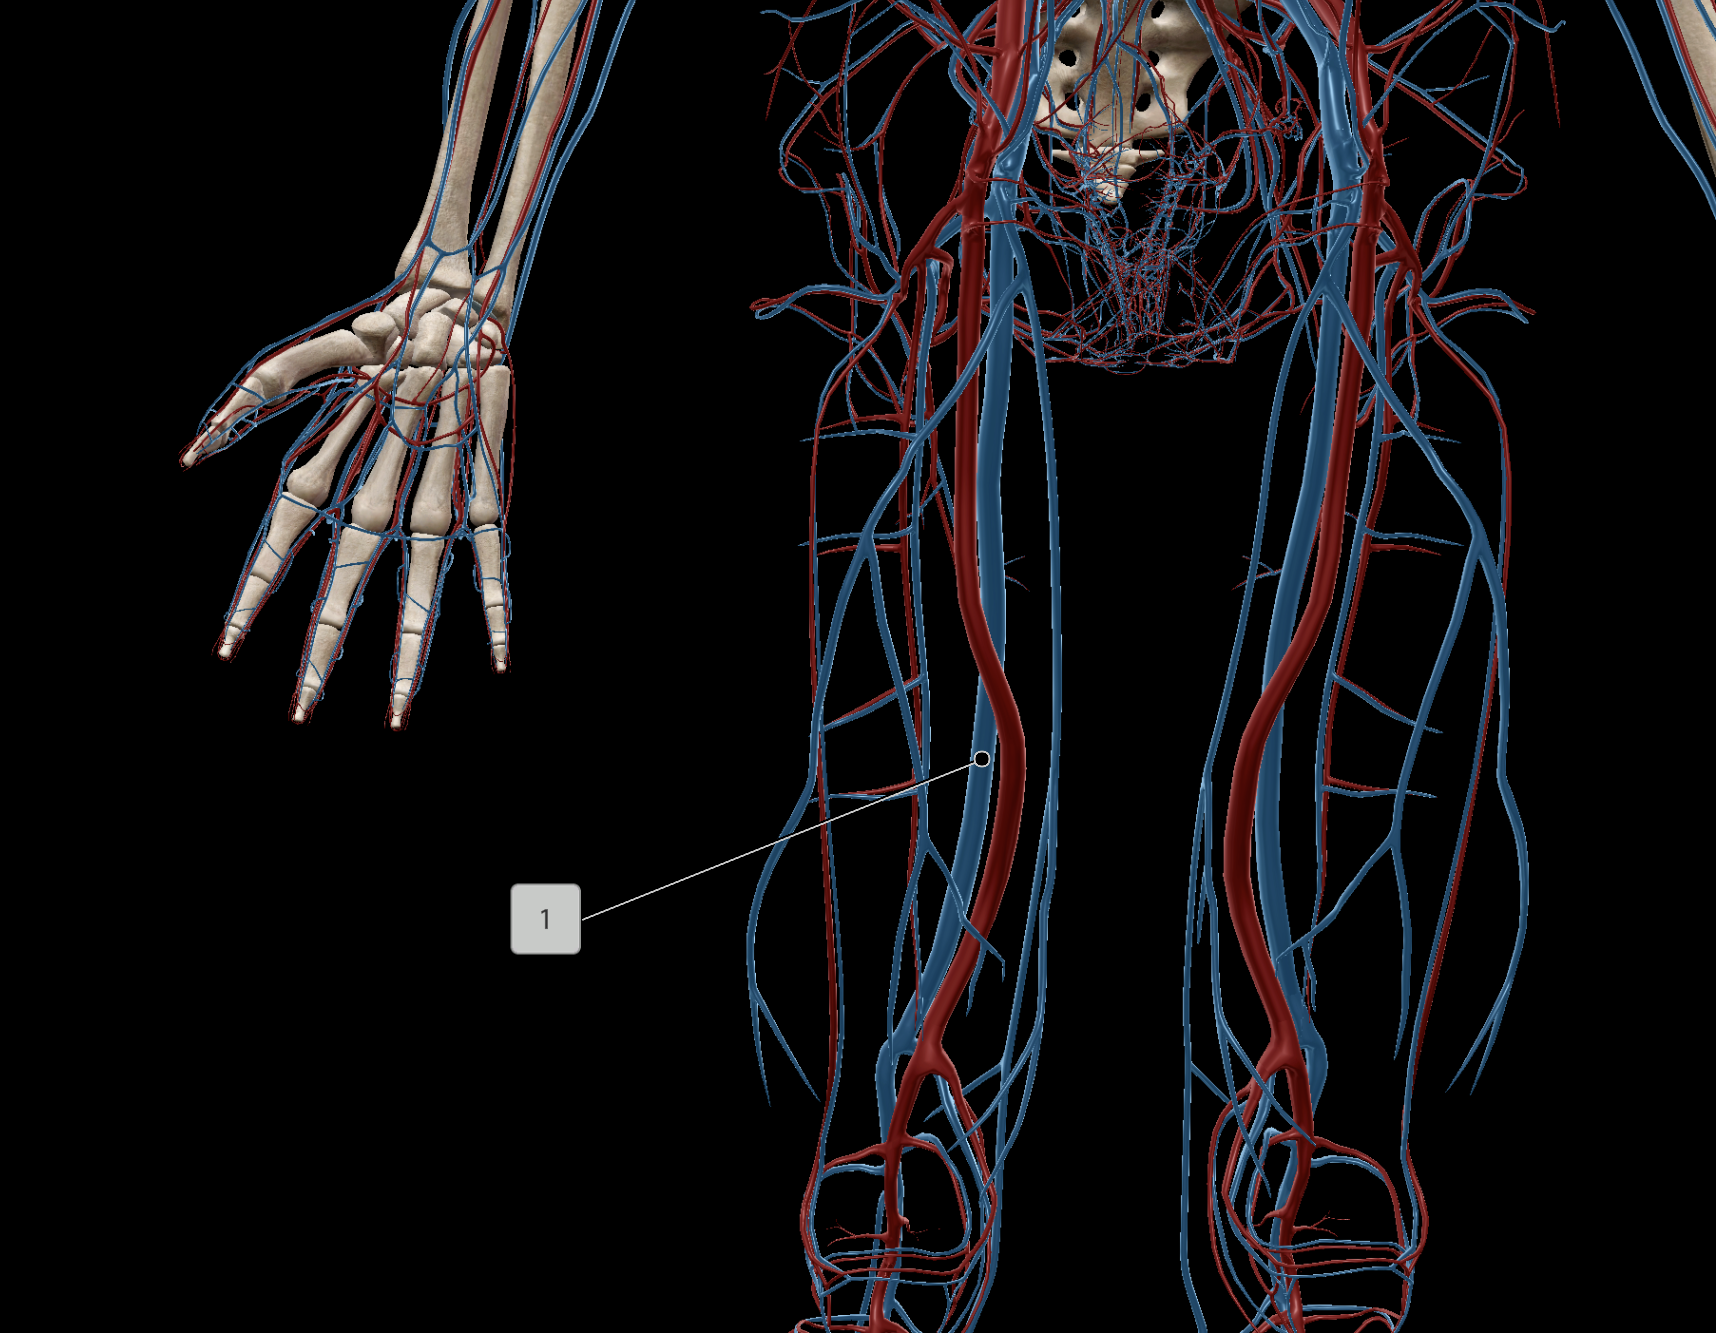

Femoral Vein

Popliteal Vein

Great Saphenous Vein

Femoral Artery

Deep Femoral Artery